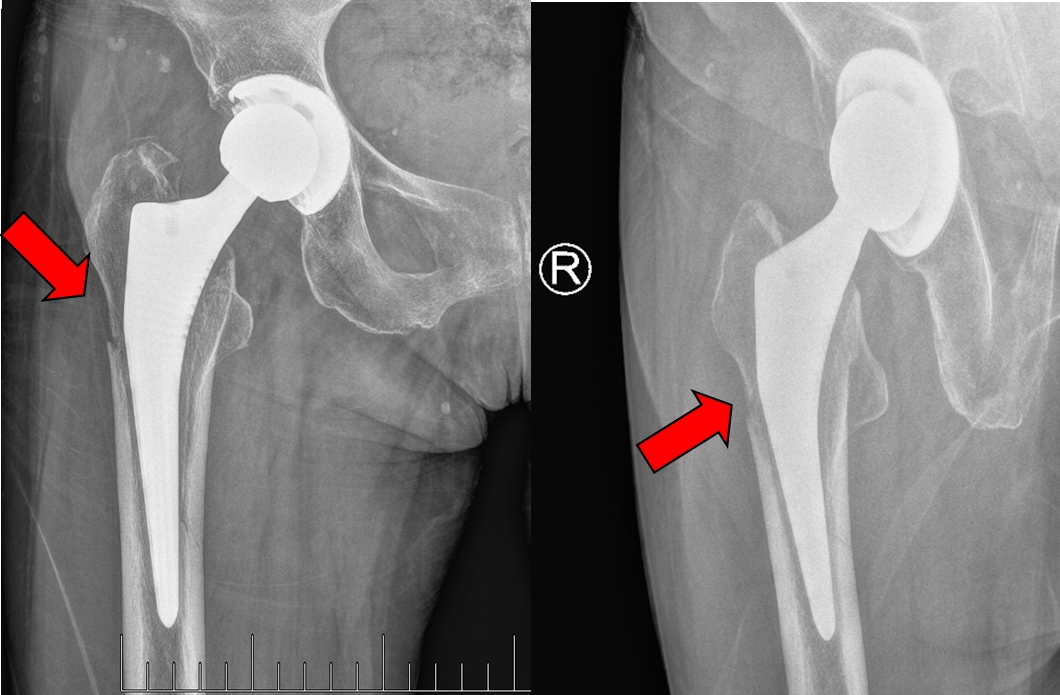

翻修术后摄片提示骨折复位满意,内固定在位